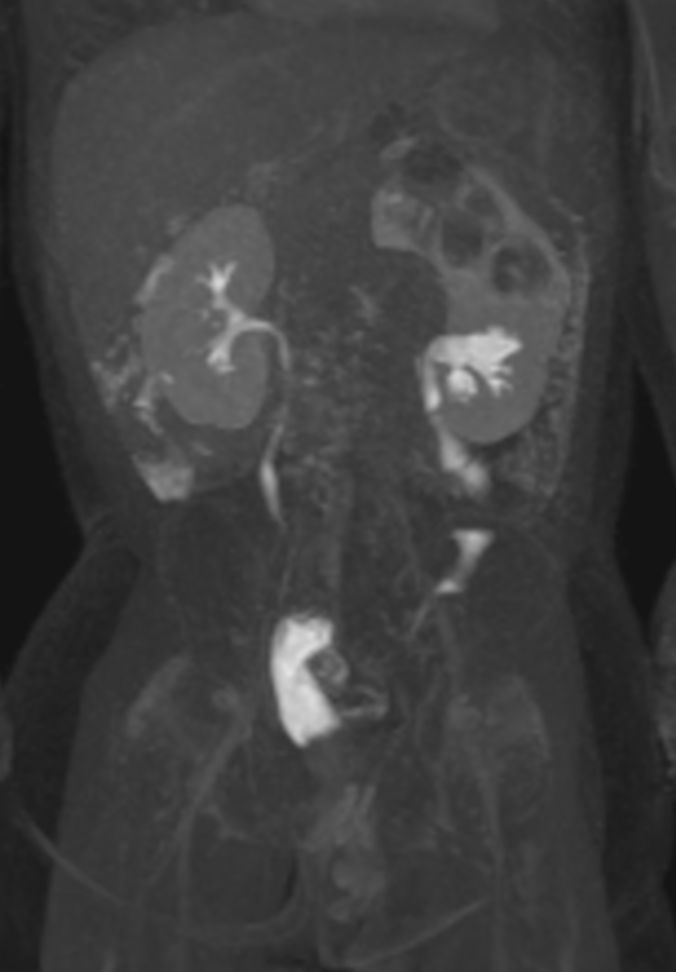

Coronal dynamic eTHRIVE